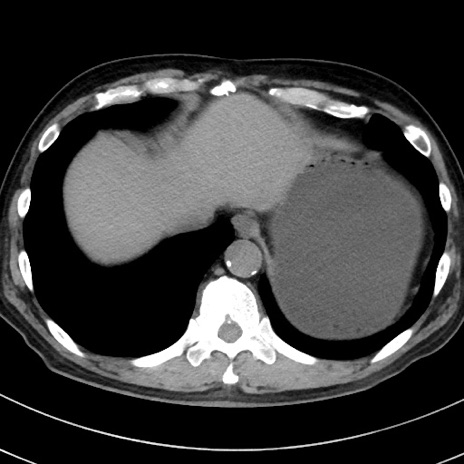

冠状断像

【症例】70歳代 男性

【主訴】腹痛・嘔吐

【現病歴】昨晩より、嘔吐・腹痛あり。今朝になっても嘔吐あり。来院。

【既往歴】心臓バイパス手術、開腹胆摘、腸閉塞

【身体所見】BP 107/71mmHg、HR 116/min、腹部:平坦、軟、下腹部に軽度圧痛あり。反跳痛なし。

【データ】WBC 15100、CRP 0.32